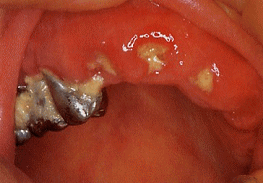

B歯牙欠損

2:義歯

義歯の有無、適合度、破損状況